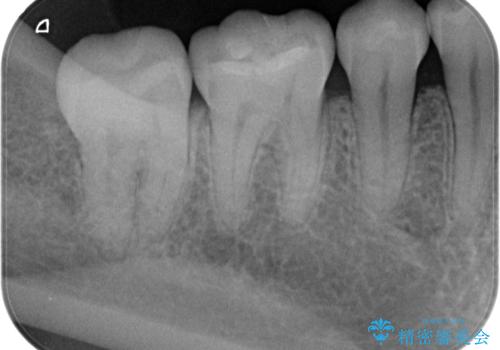

古い樹脂の劣化 セラミックインレー治療

- 保険診療での古い樹脂の劣化が気になるとの事で来院。

二つ樹脂の劣化が見られるので提案をしたが、まずは一つ治療を行いたいとの事でしたので拡大鏡下で劣化した樹脂と虫歯を取り除いた後e-maxインレーにて治療を行いました。

適合の良い詰め物が入りました。